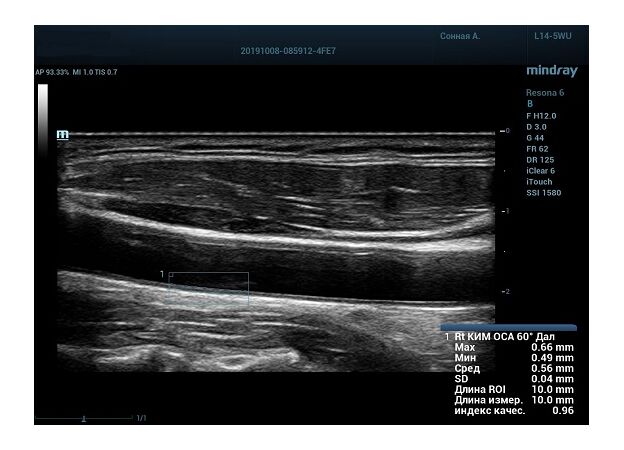

Функция в ультразвуковых аппаратах

На сегодняшний день измерение IMT происходит автоматическим путем при использовании функции AUTO-IMT. Необходимо указать прибору зону интереса, стандартной длиной (1 см), в которой происходит отслеживание кромок и выдача максимального, среднего и минимального значения. УЗИ аппараты компании Mindray среднего, экспертного и премиального класса снабжены данной функцией и позволяют контролировать не только полученные значения, но и оценить точность измерения кромки в конкретной зоне по индексу качества. Используя индекс качества, легко решить, можно ли использовать полученное значение.